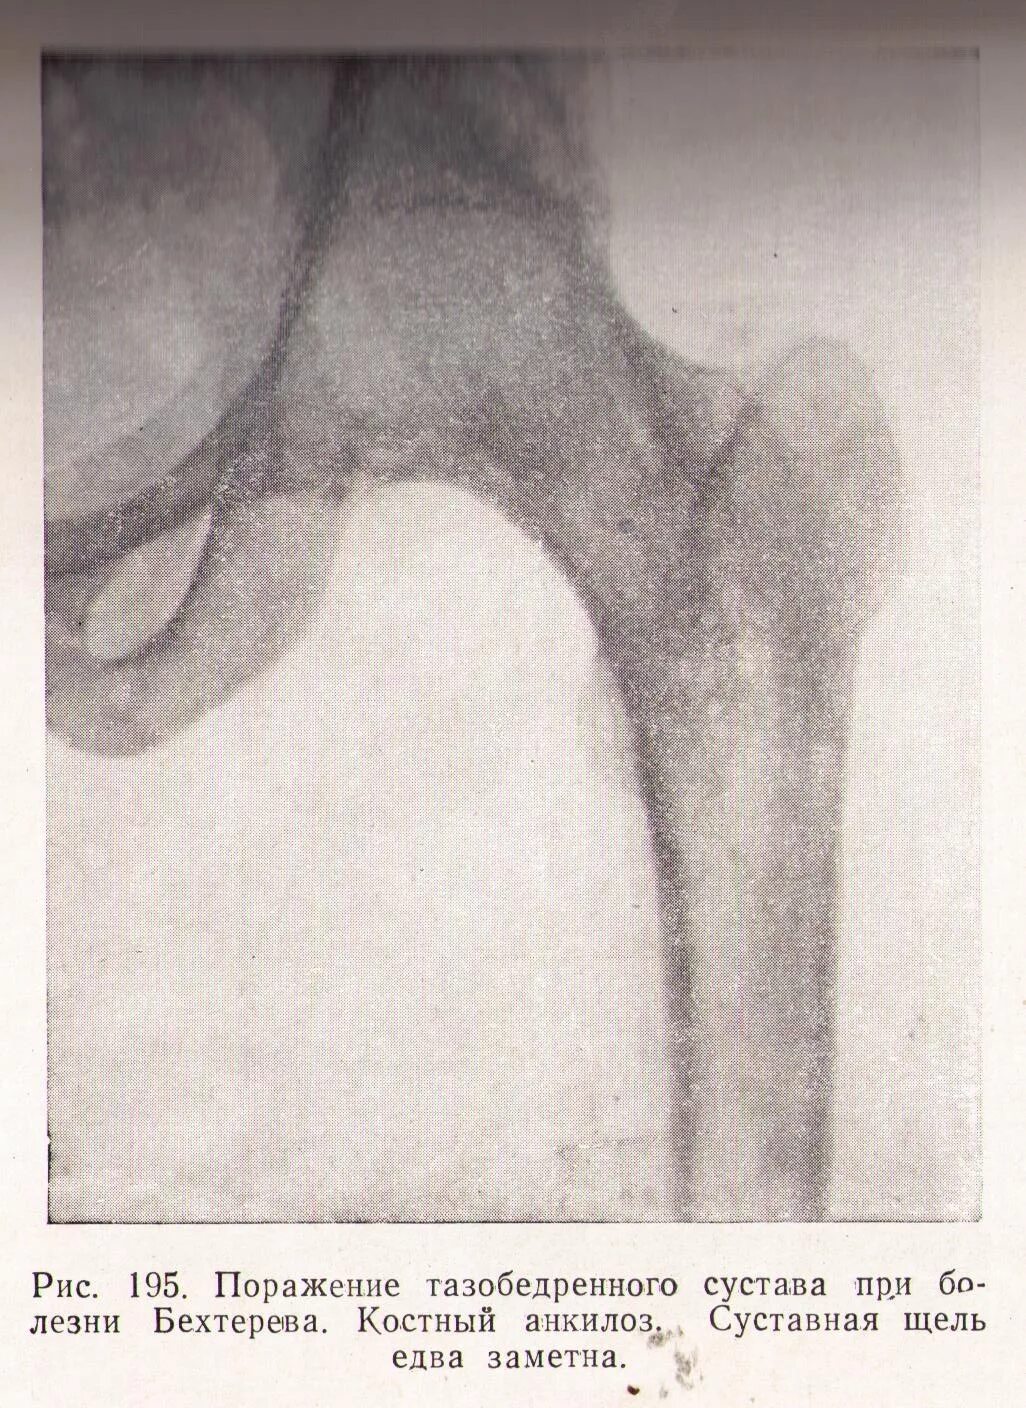

Болезнь бехтерева тазобедренных суставов